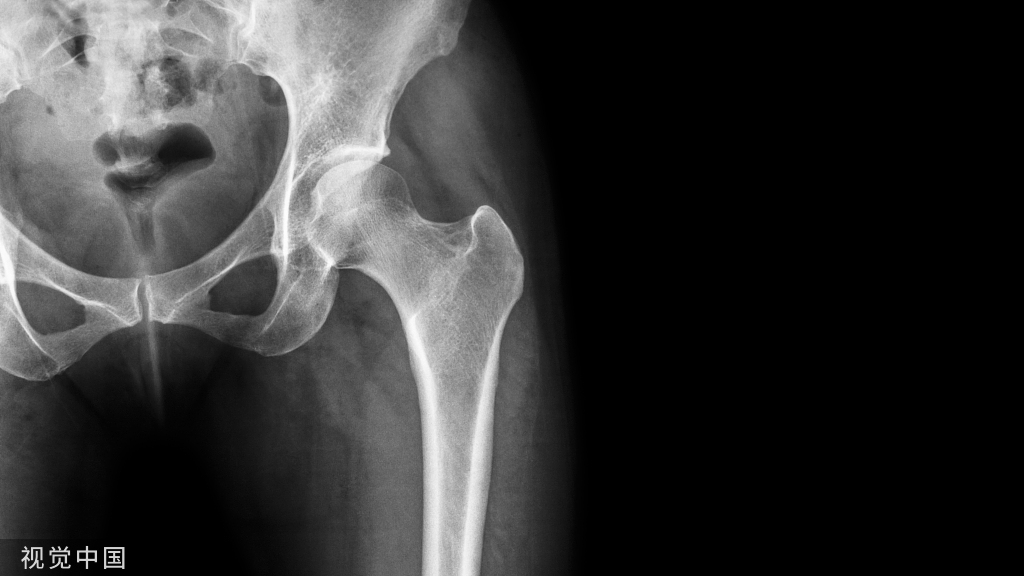

继发性骨关节病变多有创伤、感染或先天性畸形等基础病变,并与吸烟、肥胖和重体力劳动有关。病理变化为关节软骨退化变薄,软骨细胞萎缩,碎裂坏死,软骨下组织硬化,骨小梁稀疏囊性变,骨关节边缘有骨赘形成,滑膜充血水肿。

痛风患者初发时,90%侵犯单一关节,慢性期常发展为多关节炎。风湿性关节炎主要侵犯大关节,呈游走性疼痛。外伤性关节炎、骨关节炎好发在负重大的关节,如髋、膝关节。类风湿关节炎主要累及四肢小关节,尤其是近端指间关节。痛风性关节炎好发于拇趾和第一跖趾关节。

儿童和青壮年多见。负重大活动多肌肉不发达的关节易于患结核。其中脊柱最常见,其次为髋关节和膝关节。早期症状和体征不明显。活动期常有疲劳低热、盗汗及食欲下降。病变关节肿胀疼痛,但疼痛程度较化脓性关节炎轻。活动后疼痛加重。

临床上以小关节对称性累及为特点,关节呈梭形肿胀,活动期有晨僵现象,晚期关节畸形,实验室检查类风湿因子(RF)阳性,关节X线摄片对本病诊断、关节病变的分期均很重要。

外伤病史、突发性单关节疼痛,结合受累关节X线摄片容易作出诊断。